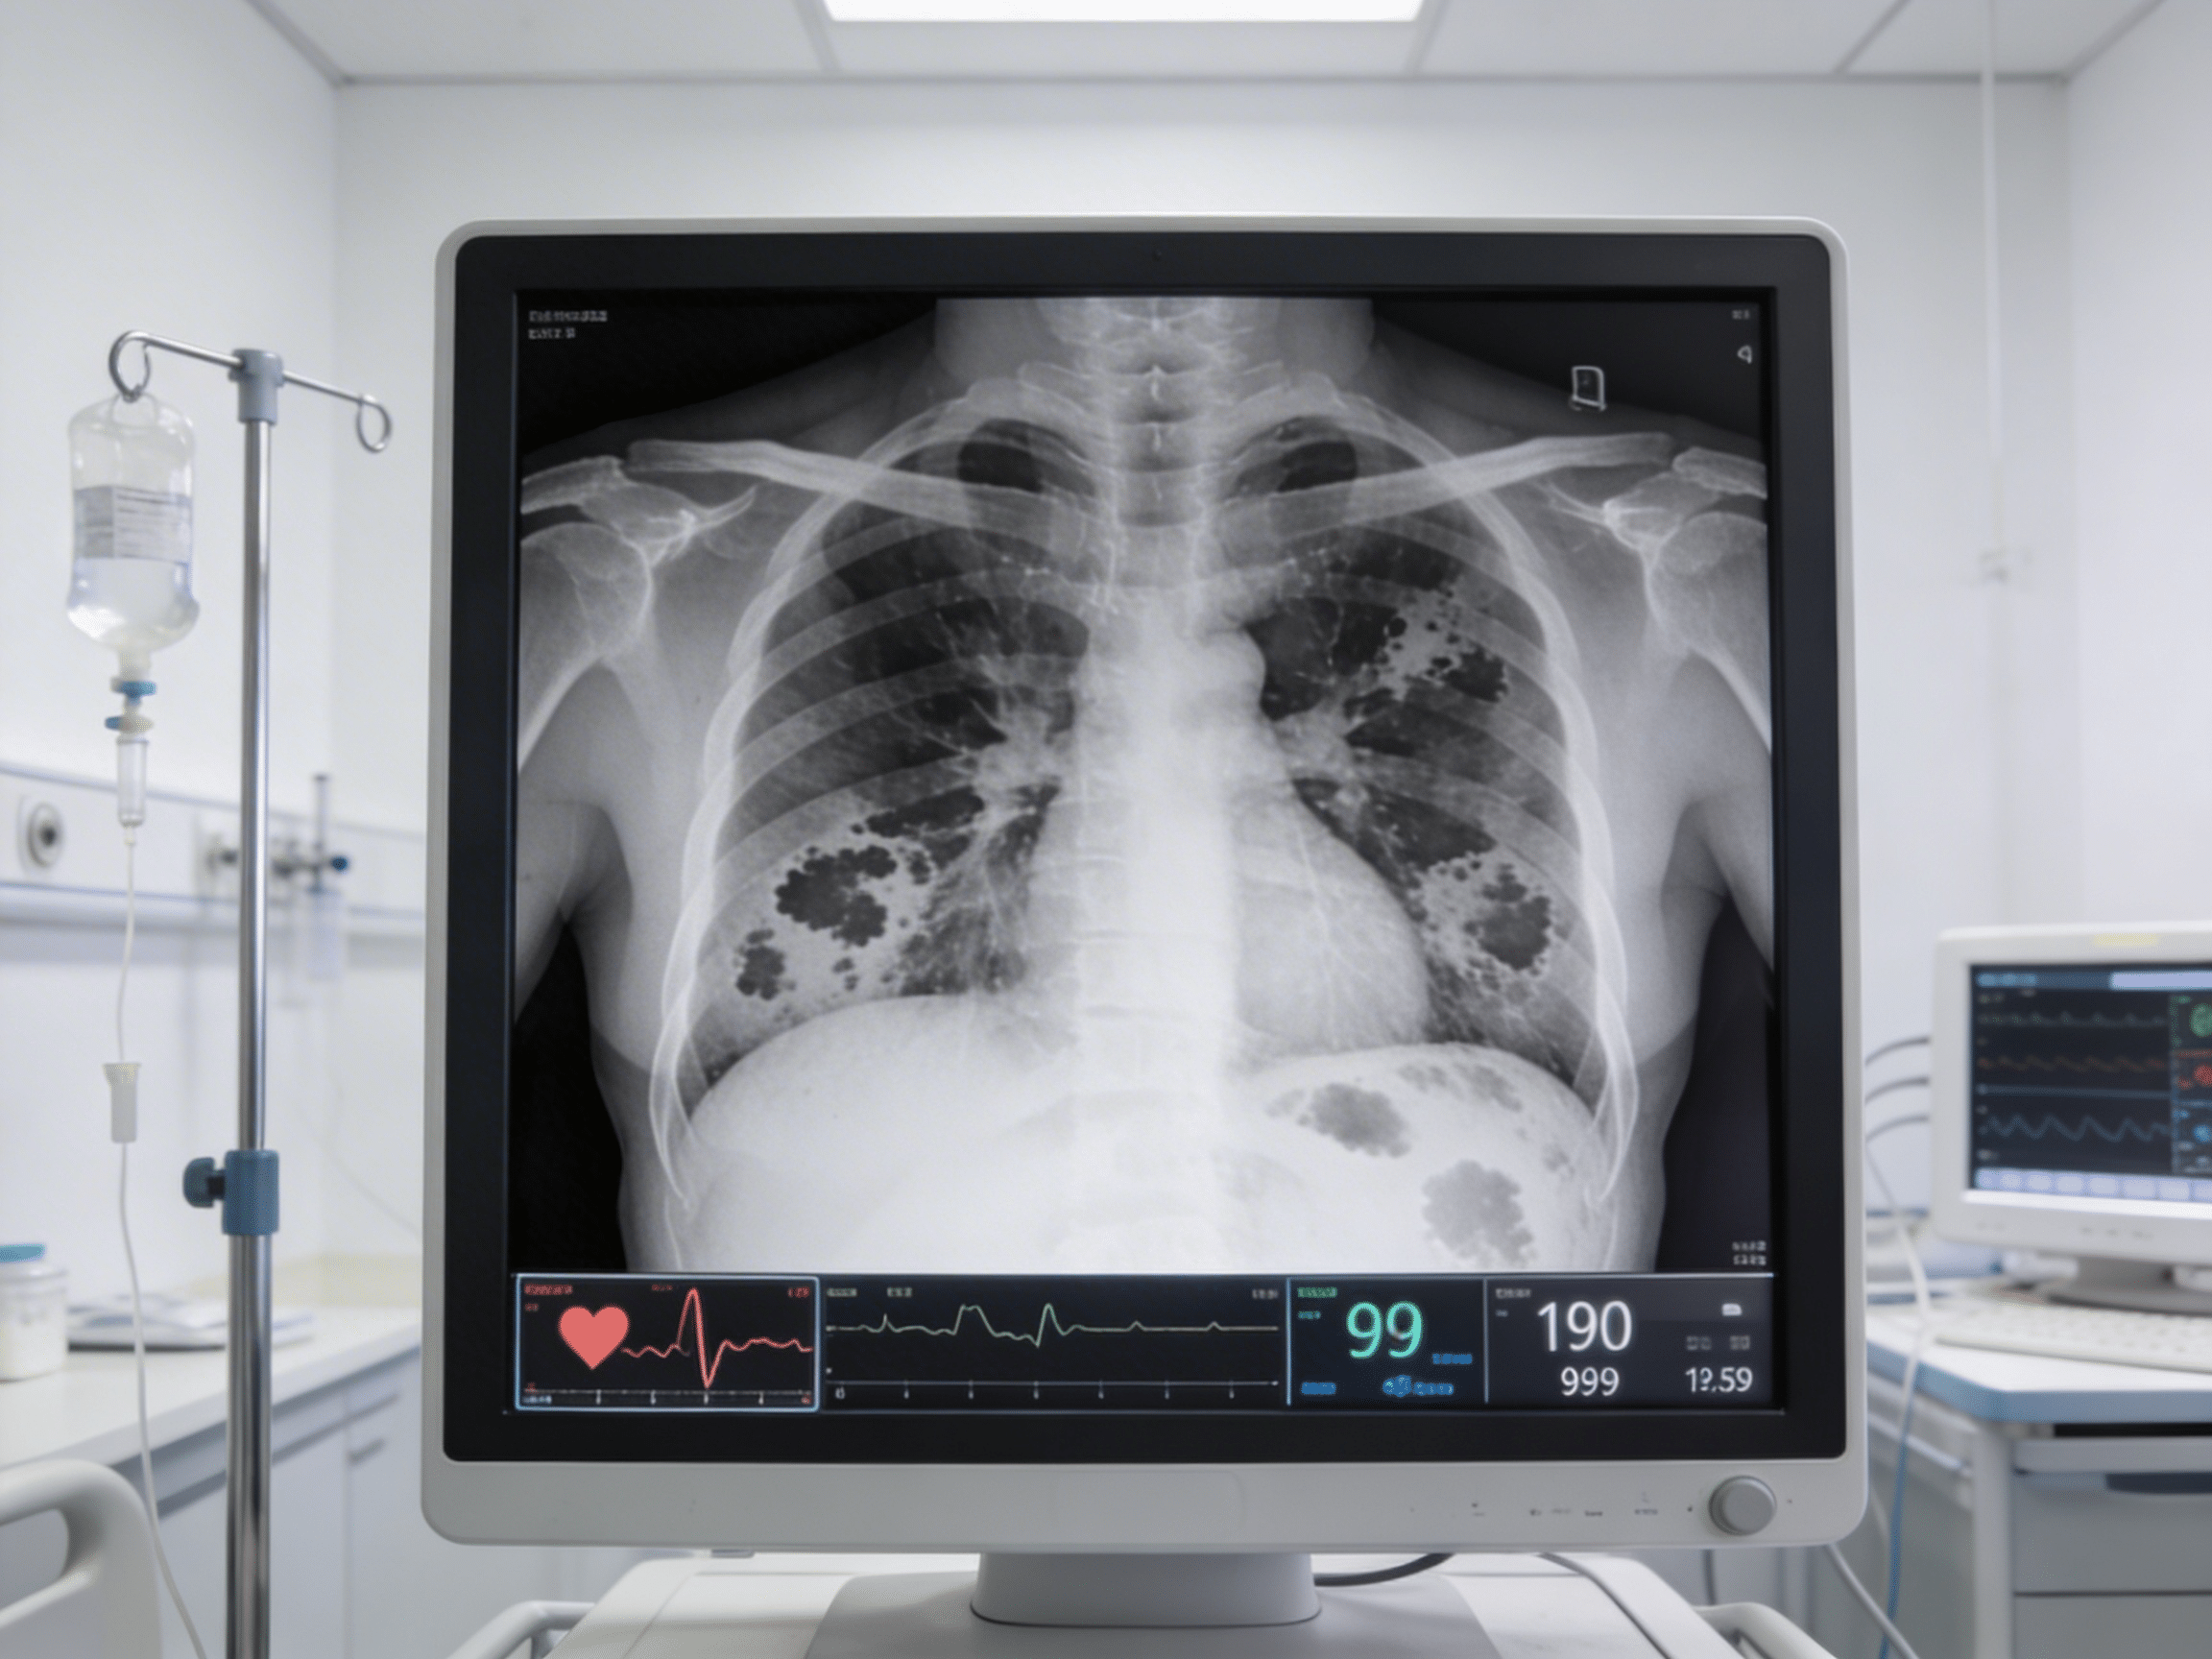

Emergency physician reviewing chest X-ray and CT angiogram at Priority ER

Board-certified emergency physicians providing immediate chest imaging interpretation and treatment

Priority ER's diagnostic capabilities for chest X-ray & CT angiogram for pneumonia, pneumothorax, or PE exceed Joint Commission standards for emergency departments[14], featuring digital portable chest radiography enabling immediate bedside imaging for unstable patients without transport to radiology, multidetector CT with IV contrast pulmonary angiography protocol detecting filling defects in pulmonary arteries with 96% sensitivity, and immediate emergency physician interpretation identifying pneumonia infiltrates, pneumothorax, and pulmonary embolism within 15 minutes. Our emergency physicians trained in chest imaging interpretation apply Wells criteria (clinical probability scoring) and PERC rule (Pulmonary Embolism Rule-out Criteria) determining which patients require CT angiography versus alternative diagnoses, preventing unnecessary radiation while ensuring PE diagnosis when clinically indicated[15]. The integration of right heart strain assessment on CT (RV/LV ratio >1.0) identifies massive PE requiring thrombolytic consideration, while identification of pneumonia complications including empyema, lung abscess, or necrotizing pneumonia guides surgical consultation.